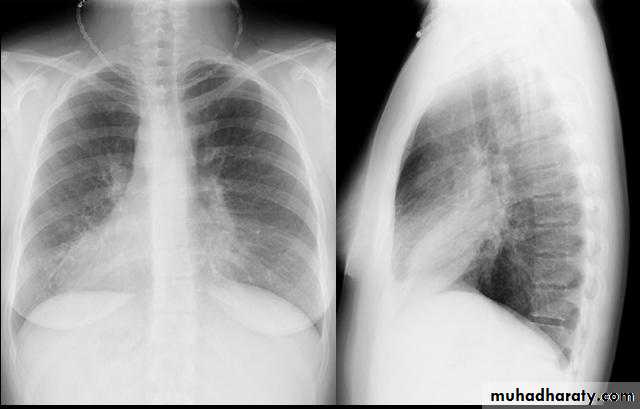

• Pathology :-A-Central type is the commonest (75%).It arises in one of the main bronchi or their primary division leading to bronchial obstruction with secondary changes in the lung such as atelectasis .B-Peripheral type (25%) arises from the smaller bronchi and remains symptom less for long time .

• Clinical features :-1- cough dry or productive2-Haemoptysis3-Chest pain4-Dyspnea5-Pleural effusion6-Anorexia & loss of weight7-Clubbing of the fingers8-Hoarseness of the voice (recurrent LN)9-Dysphagia involvement of the esophagus10-Hormonal syndromes ..ectopic ACTH , ADH, hypercalcaemia ,carcinoid syndrome

• Diagnosis

• Clinical , sputum cytology

• Chest X-ray ,CT chest ..

• Signs of inoperability :-1-Bloody pleural effusion .positive for malignant cells2-Horner’s syndrome .3-Vocal cord paralysis4-Phrenic nerve palsy(elevated hemi diaphragm)5-SVC obstruction 6-Distant metastasis 7-If during surgery ,the tumor locally spreading or cannot be remover technically or fixed to the PA or to the heart ,it is technically irresectable